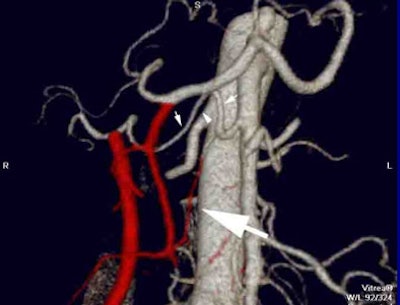

![]() |

| Color-encoded angiogram shows an aberrant origin of the right hepatic artery from the superior mesenteric artery (small arrows). As this does not cross through the surgical plane, it is not encoded although documenting its presence preoperatively is important. There is an aberrant origin of a superior pancraticoduodenal artery from this right hepatic artery (large arrow) that is predicted to traverse the surgical plane and which is subsequently color-encoded. |

The radiologist generates VR maps which are color-coded. All vessels that cross through the anticipated surgical field are color-coded in red. The finding that 40% of patients have a relevant variant, and that those with a variant had increased blood loss are key, he said.